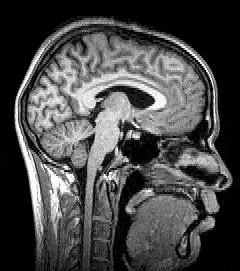

What looks paranormal is, in many cases, the visual cortex talking to itself with no outside supervision. When photoreceptors or optic nerves fail, higher visual areas lose their usual constraints and begin to free-associate, constructing scenes from fragments of stored memory. Researchers using brain imaging have seen spontaneous activity in the same regions that light up when people see real faces or objects, even though no such stimuli are present. The eerie lesson is that we do not simply “see the world”; we constantly hallucinate it, and normal vision is just the version of that hallucination that happens to be tethered to external light. Once the tether loosens, the illusion shows its seams.

Accounts of floating above one’s own body or watching oneself from the ceiling appear in near-death narratives, religious texts, and modern ER case reports alike. For centuries, these were folded into spiritual frameworks, interpreted as proof that a soul detaches from the body at the moment of crisis. Over the past two decades, however, neurologists have shown that out-of-body experiences can be triggered in surprisingly down-to-earth ways, including electrical stimulation of a region called the temporoparietal junction. This area integrates visual, tactile, and vestibular information to construct a sense of “where I am” in space. When that computation falters, the brain can misplace the self, projecting it into an illusory vantage point above or beside the body.

Advances in brain imaging, neuromodulation, and computational modeling are bringing once-mysterious experiences into sharper focus. High-resolution fMRI and invasive recordings in patients undergoing epilepsy surgery now allow scientists to watch hallucinations and out-of-body sensations unfold millisecond by millisecond across networks. Noninvasive tools like transcranial magnetic stimulation and focused ultrasound can nudge specific regions, sometimes inducing subtle distortions in body ownership or perception, offering controlled glimpses of phenomena that used to arise only by accident. Paired with sophisticated virtual reality setups, labs are probing how far a sense of self can be stretched or relocated before it snaps back. These experiments might sound like science fiction, but they are already informing therapies for chronic pain, depression, and trauma.